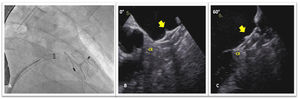

A 68-year old hypertensive man with diabetes and a history of persistent atrial fibrillation and an ischemic cerebral event, was referred for percutaneous left atrial appendage (LAA) closure. He was at high thromboembolic risk based on a CHA2DS2-VASc score of five and oral anticoagulants were contraindicated due to a firearm-related brain injury. A pre-procedure transesophageal echocardiogram (TOE) showed a LAA compatible with percutaneous closure (Figure 1A). It was performed under general anesthesia and with TOE guidance. After transseptal puncture, a windsock-shaped LAA with a landing zone of 31 mm was observed on fluoroscopy (Figure 1B). Based on TOE and fluoroscopy measurements, a 34-mm Amplatzer Amulet device was chosen and deployed in the LAA with a residual leak of 3 mm. Once in place, device stability was confirmed: tire shape of the lobe, concavity of the disk and good separation of the lobe from the disk (Figure 2-A); device lobe was aligned with appendage neck and more than two thirds of the device lobe was located distal to the circumflex artery (Figure 2B and C). The next day, he was asymptomatic and hemodynamically stable, however, a routine chest X-ray (Figure 3A) and transthoracic echocardiogram (Figure 3B and C) showed embolization of the LAA device into the left ventricular outflow tract, without impairment of mitral valve function. Because of the risk of damage to the aortic and mitral valves by the device unfolded anchoring barbs, urgent surgical device removal (Figure 4) and appendage amputation was the first line strategy and the procedure was uneventful.